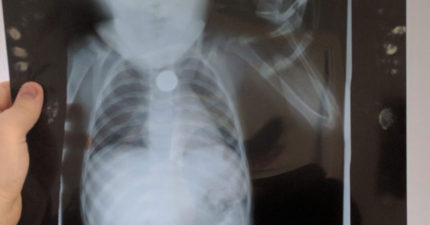

他上傳了「2歲時錢幣卡在喉嚨裡的X光照」,網友眼尖看到了最令人爆感動的溫馨亮點。